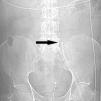

A patient underwent CRRT throw a left femoral vein catheter (34cm–13.5F). Immediately after the insertion we detected problems in the circuit blood flow and the patient deteriorated. A CT scan showed the tip of the catheter in the left lumbar vein beside a retroperitoneal haematoma (Fig. 1). Another patient (same catheter and insertion technique) showed persistent blood flow problems and in a CT scan the catheter was detected in an accessory left hemiacygos vein and already visible in the plain abdominal X-ray (Fig. 2). Because presumably an eco-directed insertion would not have prevented these anomalous locations, in the event of serious flow problems, a radiologic exploration can help ruling out this unusual and scarcely reported malposition that demands immediate withdrawal of the catheter.